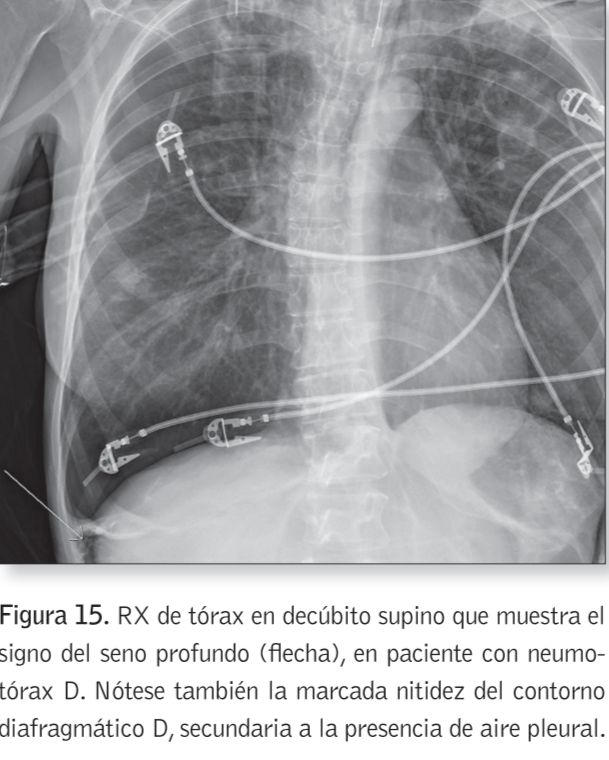

Signo del seno profundo